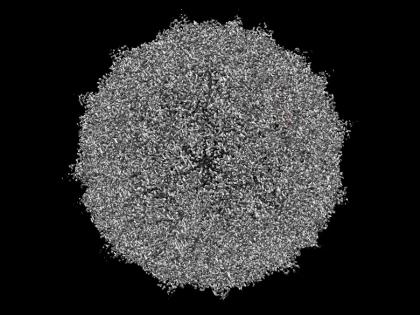

२१ लोकांना कोरोना व्हायरसची लागण झाली होती. जगभरात ७ प्रकारच्या कोरोना व्हायरस दिसून आले आहेत. परदेशातून आलेल्या १५ लोकांमध्ये रायनो हा व्हायरस दिसून आला होता. कोरोना व्हायरसप्रमाणे ५ ते ७ दिवसांनी व्हायरसची लक्षणं दिसून येतात.